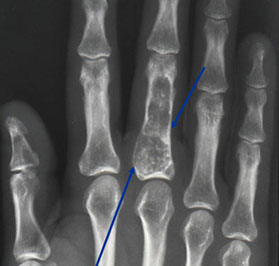

Bizarre Parosteal Osteochondromatous Proliferation (BPOP)

- aka Nora's lesion

Rare, aggressive tumor in soft tissue of hands and feet adjacent to bone that resembles osteochondroma on imaging

Arises directly from cortex and lacks the continuity bwt lesional and cortical bone as in osteochondroma

Micro: Lobulated, cellular cartilagenous tissue c calcified fibrocartilagenous tissue at periphery; also c bone and fibrous tissue

DDx: florid reactive periostitis, subungual exostosis

- these are assoc c trauma; BPOP is not, however

BPOP